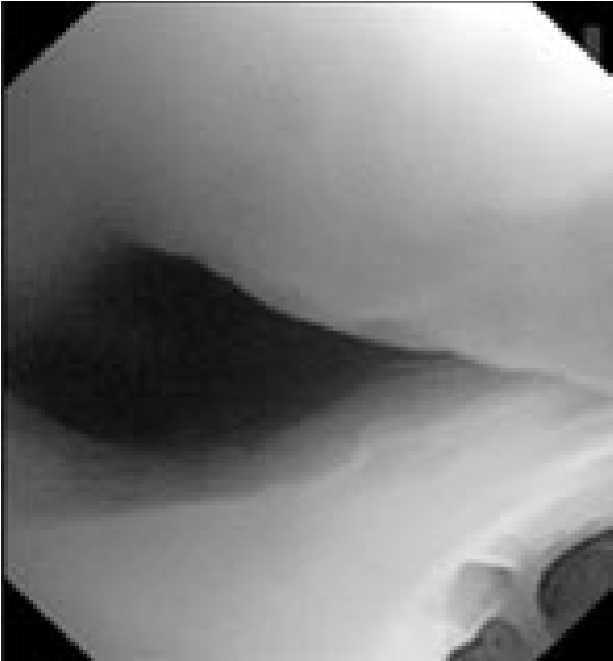

От предложенной по месту жительства эксплоративной операции (торакотомия) пациент отказался и самостоятельно обратился в консультативно-поликлиническое отделение (КПО) ФБГНУ «ЦНИИТ» для уточнения диагноза. При обследовании в КПО реакция на пробу Манту с 2ТЕ ППД-Л через 72 ч – отрицательная, реакция на пробу с АТР (антиген туберкулезный рекомбинантный) через 72 ч – отрицательная. Клинический анализ крови и мочи – без особенностей. По данным КТ ОГК от 22.08.2017 г., у пациента выявлены сочетанная аденопатия средостения, преимущественно с поражением групп лимфоузлов 2R, 4R, 7, 4L, а также дистелектаз S1-2 и S3 левого легкого, связанный с аденопатией (рис. 1)2

Рис. 1. Аксиальные срезы компьютерной томограммы в легочном (а) и средостенном (б) режимах пациента А.